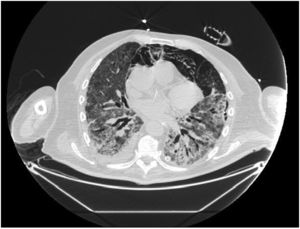

In our study, CT was used to identify and confirm spontaneous PM and PM relative to mechanical ventilation. The scannographic signs of PM relied on the anatomical region occupied by the air as it exits the mediastinum.20 (Figs 1, 2).

Pneumomediastinum (PM) is a condition where the air is present in the mediastinum. Free air leaks from ruptured alveoli, dissecting along the bronchovascular sheaths towards the mediastinum. PM, as seen on chest CT, elevates the mediastinal pleura and can extend into the neck or chest wall.14 One of the first signs that simulate a pneumomediastinum is the Mach band effect. This optical effect at the margin between areas of faintly different density15 can mimic various other pathologies (pneumopericardium, fracture), and makes it possible to suspect PM in COVID-19 patients. Non-traumatic PM is a rare complication of COVID-19 pneumonia.16 Its development in COVID-19 infection is also considered a possible indicator of disease worsening, which may be or not be associated with invasive ventilatory support. Spontaneous PM seemed to be a frequent complication of severe acute respiratory syndrome (SARS).17 In 2004, a high peak LDH level of 863 IU/L had been correlated with spontaneous PM in SARS patients, likely due to significant remodeling of the lung tissue causing leakage and vessel wall dissection.17 Most patients with PM had lung involvement higher than 50% at the moment of the diagnosis,18 corroborating the increased risk of rupture and PM development. This study aimed to evaluate the association between baseline serum LDH levels and COVID19 lung necrosis outcome based on the extent of lobar involvement and PM development.